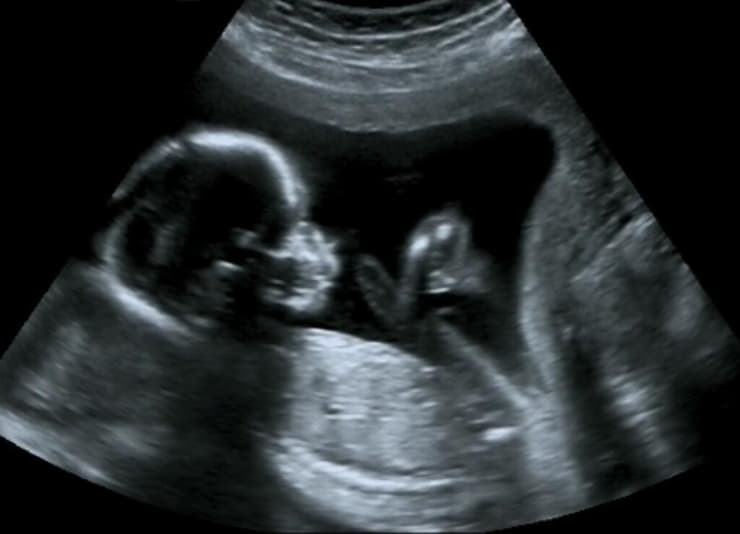

דויילי, דולה מקצועית לליווי לידות, לא הייתה מעוניינת בכך, ועמדתה בנושא היתה נחרצת. היא כבר עברה שלושה ניתוחים קיסריים בעבר, שאחד מהם הסתיים בדימום משמעותי, והיא קיוותה להימנע מסיבוך נוסף ומהחלמה ממושכת. היא ידעה שהרופאים חוששים מפני קרע ברחם - סיבוך שעלול להיות קטלני לה ולעובר. במהלך הדיון אמרה כי להבנתה הסיכון לכך נמוך מ-2%, וכי אינה מוכנה להסכים לניתוח קיסרי, אלא אם יתפתח מצב חירום.

ד"ר ארין ברנט אמרה במהלך הדיון כי אינה חושבת שדויילי תוכל ללדת בהצלחה בלידה וגינלית, משום שיש לה היסטוריה של לידות שנתקעו. לידה ממושכת לאחר ניתוחים קיסריים קודמים עלולה להעלות את הסיכון לקרע ברחם, שעלול להרוג את דוילי ואת הילד, אמרה. לדבריה, קצב הלב של התינוק הראה כמה סימנים למצוקה, והיא אמרה לדויילי שעדיף לבצע ניתוח קיסרי לפני שהמצב יהפוך לחירום. אם לב התינוק יפסיק לפעום או אם יסבול מחוסר חמצן במהלך הלידה, הוא עלול לסבול מפגיעה מוחית או ממוות. ד"ר ג'ון דייוויס, יו"ר המחלקה למיילדות ולגינקולוגיה, העיד כי בית החולים נודע בשיעור נמוך של ניתוחים קיסריים ואינו מבצע ניתוחים מיותרים. מצבה של דויילי, לדבריו, הצריך התערבות.

ברנט ודייוויס לא השיבו לבקשות לתגובה, ובית החולים דחה את בקשות ProPublica לראיין אותם ואחרים שהיו מעורבים בטיפול בדויילי. דווילי חתמה על ויתור סודיות שאפשר לבית החולים לדון במקרה שלה עם ProPublica, אך דובר מטעם University of Florida Health בג'קסונוויל סירב להגיב, בנימוק של פרטיות המטופלת. בית החולים גם לא השיב לשאלות על טענתה של דויילי כי לגזע היה חלק בהחלטה לערב את בית המשפט. המחקר על הסיכון לקרע ברחם לאחר ניתוחים קיסריים קודמים אינו חד-משמעי. מחקרים מצאו שבין 0.15% ל-2.3% מלידות כאלה הסתיימו בקרע, תלוי בשורה של גורמים כמו מאסת הגוף, היסטוריה של לידות וגינליות מוצלחות ואם הלידה החלה באופן ספונטני או שהייתה מושרית.